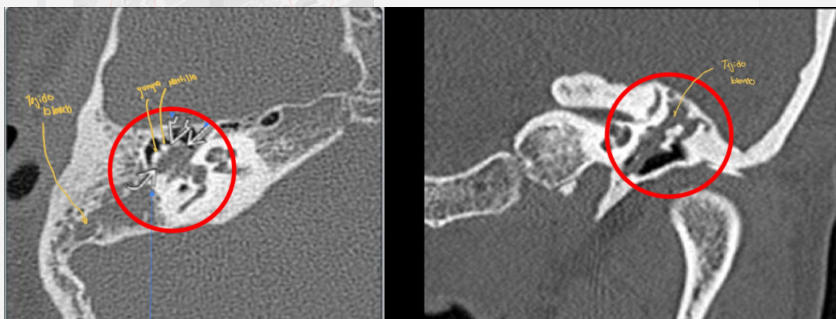

Dx de la siguiente imagen

A

Mastoiditis

Clave en imagneología para dx de mastoiditis

Opacificación de celdillas mastoideas+ colección de líquido (pus o moco)

Si es crónico vemos efecto esclerodiploico que es mastoides osificada